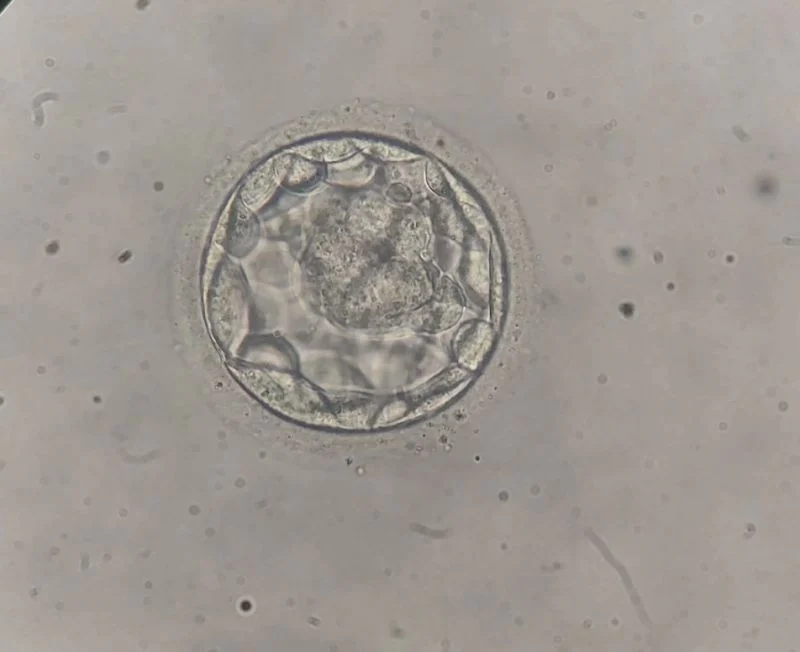

Mahmoud Elhusseini: Day 5 Blastocyst Insights from Top Embryologist

Mahmoud Elhusseini, Senior Embryologist at Ganna Hospital, shared a post on LinkedIn:

“Single embryo transfer

Day 5 Blastocyst ”